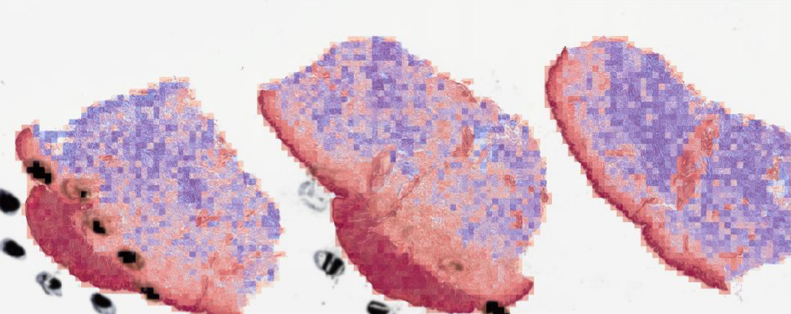

3.3 Misclassified Slides Discussion

The proposed method PCLA-3C only misclassified two slides in the testing set. The two WSIs are both labeled as nevus but misclassified as melanoma by the model (see the two slides and corresponding visualization results in Fig. 4 and Fig. 5). The slide in Fig. 4 is not a typical nevus and it has the features of a pigmented spindle cell nevus, which is one diagnostic challenge of melanocytic skin tumor. However, the slide in Fig. 5 is a routine type of nevus. The reason that PCLA-3C misclassified the slide could be based on the difference in color. In general, the ROIs in melanoma cases were dark, while those in nevus cases were light. As shown in Fig. 7b, there were some dark areas outside the annotated ROIs, which contributed to the misclassification of slides and the incorrect detection of ROIs.

(a) Original WSI

(b) Overlay

(c) Heatmap